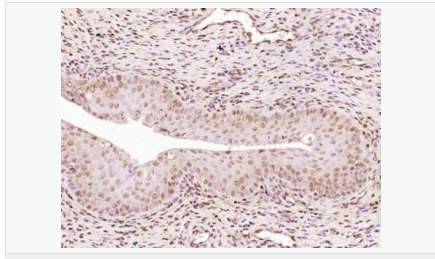

| 產(chǎn)品應用 | WB=1:500-2000 IHC-P=1:100-500 IHC-F=1:100-500 Flow-Cyt=1ug/Test ICC=1:100-500 IF=1:100-500 (石蠟切片需做抗原修復) not yet tested in other applications. optimal dilutions/concentrations should be determined by the end user. |

| 細胞定位 | 細胞核 細胞漿 |

| 產(chǎn)品介紹 | Estrogen and progesterone receptor are members of a family of transcription factors that are regulated by the binding of their cognate ligands. The interaction of hormone-bound estrogen receptors with estrogen responsive elements(EREs) alters transcription of ERE-containing genes. The carboxy terminal region of the estrgen receptor contains the ligand binding domain, the amino terminus serves as the transactivation domain, and the DNA binding domain is centrally located. Two forms of estrogen receptor have been identified, ER alpha and ER beta. ER alpha and ER beta have been shown to be differentially activated by various ligands. The biological response to progesterone is mediated by two distinct forms of the human progesterone receptor (hPR-Aand hPR-B), which arise from alternative splicing. In most cells, hPR-B functions as a transcriptional activator of progesterone-responsive gene, whereas hPR-A function as a transcriptional inhibitor of all steroid hormone receptors. Function: The steroid hormones and their receptors are involved in the regulation of eukaryotic gene expression and affect cellular proliferation and differentiation in target tissues. Progesterone receptor isoform B (PRB) is involved activation of c-SRC/MAPK signaling on hormone stimulation. Isoform A is inactive in stimulating c-Src/MAPK signaling on hormone stimulation. Subunit: Interacts with SMARD1 and UNC45A. Interacts with CUEDC2; the interaction promotes ubiquitination, decreases sumoylation, and repesses transcriptional activity. Interacts with PIAS3; the interaction promotes sumoylation of PR in a hormone-dependent manner, inhibits DNA-binding, and alters nuclear export. Interacts with SP1; the interaction requires ligand-induced phosphorylation on Ser-345 by ERK1/2 MAPK. Interacts with PRMT2. Subcellular Location: Nucleus. Cytoplasm. Note=Nucleoplasmic shuttling is both homone- and cell cycle-dependent. On hormone stimulation, retained in the cytoplasm in the G(1) and G(2)/M phases. Isoform A: Nucleus. Cytoplasm. Note=Mainly nuclear. Post-translational modifications: Phosphorylated on multiple serine sites. Several of these sites are hormone-dependent. Phosphorylation on Ser-294 occurs preferentially on isoform B, is highly hormone-dependent and modulates ubiquitination and sumoylation on Lys-388. Phosphorylation on Ser-102 and Ser-345 also requires induction by hormone. Basal phosphorylation on Ser-81, Ser-162, Ser-190 and Ser-400 is increased in response to progesterone and can be phosphorylated in vitro by the CDK2-A1 complex. Increased levels of phosphorylation on Ser-400 also in the presence of EGF, heregulin, IGF, PMA and FBS. Phosphorylation at this site by CDK2 is ligand-independent, and increases nuclear translocation and transcriptional activity. Phosphorylation at Ser-162 and Ser-294, but not at Ser-190, is impaired during the G(2)/M phase of the cell cycle. Phosphorylation on Ser-345 by ERK1/2 MAPK is required for interaction with SP1. Sumoylation is hormone-dependent and represses transcriptional activity. Sumoylation on all three sites is enhanced by PIAS3. Desumoylated by SENP1. Sumoylation on Lys-388, the main site of sumoylation, is repressed by ubiquitination on the same site, and modulated by phosphorylation at Ser-294. Similarity: Belongs to the nuclear hormone receptor family. NR3 subfamily. Contains 1 nuclear receptor DNA-binding domain. SWISS: P06401 Gene ID: 5241 Database links: Entrez Gene: 5241 Human Entrez Gene: 18667 Mouse Entrez Gene: 100009094 Rabbit Omim: 607311 Human SwissProt: P06401 Human SwissProt: Q00175 Mouse SwissProt: P06186 Rabbit Unigene: 2905 Human Unigene: 32405 Human Unigene: 742403 Human Unigene: 12798 Mouse Unigene: 437703 Mouse Unigene: 1947 Rabbit Unigene: 10303 Rat Important Note: This product as supplied is intended for research use only, not for use in human, therapeutic or diagnostic applications. |